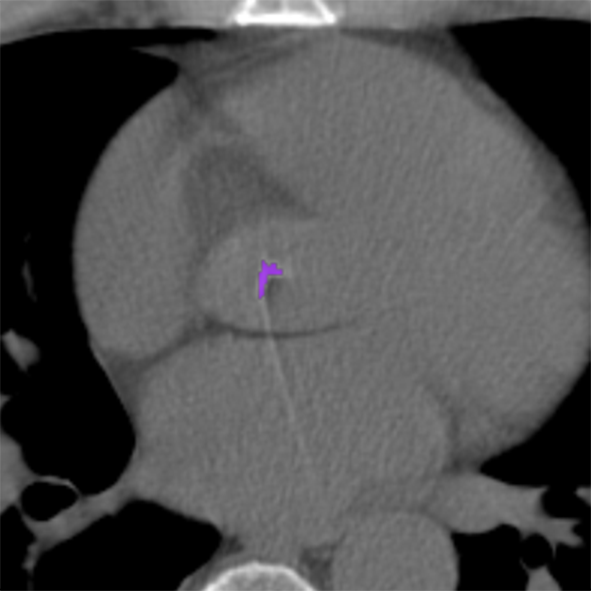

To establish a reference standard, calcifications were manually labeled in all scans. Scans were distributed among four trained observers and one radiologist with extensive experience in calcium scoring. To measure interobserver agreement, a subset of 100 scans (four scans from each of the 25 different scanner models and reconstruction algorithms) was annotated by two of the trained observers and the radiologist. Manual calcium annotation usually requires the observer to select only a single voxel per lesion. The lesion is then automatically segmented with region growing using the standard intensity threshold of . In low-dose scans, however, intensity based region growing often leads to large amounts of noise being segmented with the calcium (Figure 1). Moreover, it can lead to the spine and ribs being segmented together with calcium, or calcifications in arteries branching off the aorta being segmented together with calcium in the aorta. The observers therefore marked calcifications voxel-by-voxel () in the coronary arteries, the aorta and the aortic and mitral valves, including the annulus. Coronary calcifications were labeled as either left anterior descending artery (LAD), left circumflex artery (LCX) or right coronary artery (RCA). The left main coronary artery was considered part of LAD because these are difficult to distinguish on ungated scans. Motion artifacts caused by calcifications were annotated as calcifications because an exact separation of true calcification and artifact is often not possible. Depending on the amount of calcification and the image quality, the annotation effort varied from 5–10 minutes for images with soft reconstruction and little calcium to 60–90 minutes for images with sharp reconstruction and/or large amounts of calcium.

The performance of automatic CAC detection was evaluated based on scores per artery and per subject. Per artery and per subject sensitivities, average false positive volumes and F1 scores for CAC detection are listed in Table II. Examples of detected calcifications are shown in Figure 6.

(a)

(b)

(c)

(d)

(e)

(f)

(g)

(h)

(i)

(j)

(k)

(l)

For CAC and TAC detection, the method achieved a performance close to the level of interobserver agreement. The method was furthermore able to separate calcifications in the coronary arteries into LAD, LCX and RCA calcifications (Figure 6 (f)). The method as well as the observers were more successful in identification of LAD and RCA calcifications than LCX calcifications. The course of LCX is particularly difficult to follow in non-contrast scans. Hence, LCX calcifications can be difficult to differentiate from LM and LAD calcifications (Figure 6 (l)), as well as from those in the mitral valves. In comparison to CAC and TAC, calcifications of the aortic and mitral valves were less common in our dataset. Performance of the automatic method was below the performance of CAC and TAC detection. However, this is also a difficult task for experts. The observers especially disagreed on mitral valve calcifications, which is in line with findings of previous studies [45]. The disagreement is mainly caused by confusion with LCX calcifications and the lack of soft tissue contrast in the mitral valve region. For the aortic valve, confusion with TAC was the most common cause of disagreement.

False positive detections were mostly caused by mislabeling of calcifications with respect to their location (e.g., LAD and LCX), low-dose and motion artifacts, and other calcifications such as calcified lymph nodes or calcifications in other vessels (Figure 6 (i)–(k)). False positive detections outside the heart and the aorta occurred infrequently and usually in proximity to the heart or the aorta. This demonstrates that CNN1 was able to implicitly learn to recognize the typical spatial context of calcifications in the image. The individual evaluation of CNN1 additionally showed that CNN2 substantially contributes to reducing false-positive detections while maintaining a high sensitivity. However, future work could aim at unifying the two networks into a single network.

False negative detections were sometimes partially misclassified lesions (Figure 6 (h)–(i)). Partial misclassification can occur because the method performs voxel classification rather than the standardly used lesion classification. Even though voxel labeling occasionally causes partial misclassification of calcifications, it enables splitting of calcifications that are contained in more than one arterial bed, such as those partly located in the aorta and partly in the coronary arteries (Figure 6 (f)). Assigning a calcification that is partially contained in the aorta to the coronary artery could affect cardiovascular risk categorization. Similarly, assigning LM calcifications to the aorta would result in missing high risk lesions. To the best of our knowledge, this is the first method enabling splitting of the calcifications according to their arterial bed.